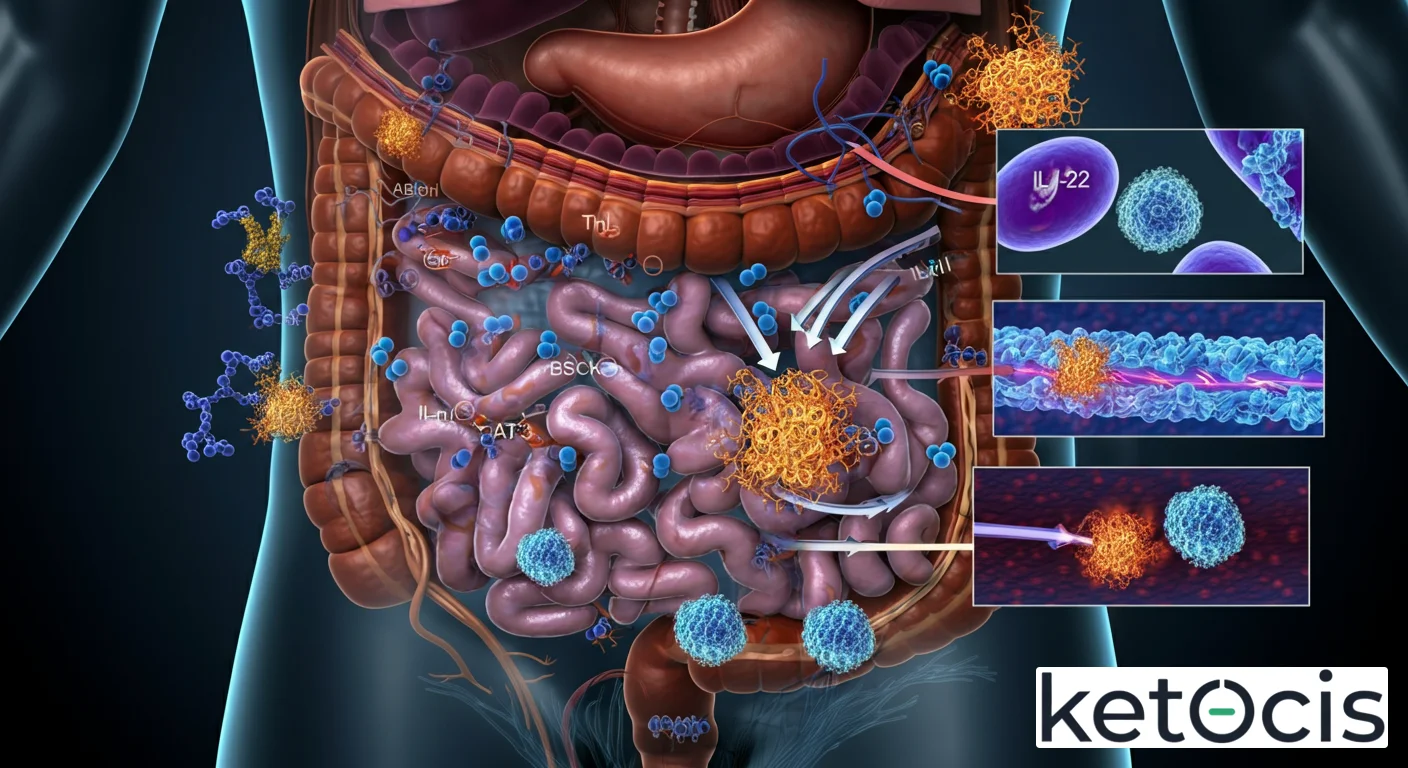

En el vasto y complejo universo de la inmunología, donde cada molécula orquesta una sinfonía de defensa y reparación, la interleucina-22 (IL-22) emerge como una protagonista de particular fascinación. Lejos de ser una mera pieza en el engranaje, esta citoquina, perteneciente a la familia de la interleucina-10 (IL-10), desempeña un papel irremplazable en la protección de nuestras superficies corporales, desde la piel hasta el intrincado revestimiento intestinal. Su singularidad radica no solo en su capacidad para modular la respuesta inmune, sino, y quizás más críticamente, en su habilidad para comunicarse directamente con células no inmunes, como las células epiteliales, promoviendo su supervivencia, proliferación y la producción de factores antimicrobianos. Comprender la IL-22 es desentrañar una capa fundamental de nuestra resiliencia biológica, un pilar que sostiene la integridad de nuestras barreras frente a un mundo lleno de desafíos microscópicos, y un factor clave en la homeostasis metabólica, especialmente relevante en el contexto de estrategias como la dieta cetogénica y el ayuno intermitente.

Mecanismo de Acción: Cómo la IL-22 Protege y Repara

El poder de la IL-22 reside en su capacidad para activar vías de señalización específicas en sus células diana. Su receptor, conocido como IL-22R, es un heterodímero compuesto por dos subunidades: IL-22R1 y la cadena común IL-10R2, esta última compartida con otros receptores de la familia IL-10. Una vez que la IL-22 se une a su receptor en la superficie de una célula, se desencadena una cascada de eventos intracelulares que culmina en cambios en la expresión génica.

La vía de señalización predominante activada por la IL-22 es la vía JAK/STAT, específicamente la activación de las quinasas JAK1 y Tyk2, que a su vez fosforilan la proteína STAT3 (Signal Transducer and Activator of Transcription 3). La fosforilación de STAT3 es un evento central, ya que permite que esta proteína se trasloque al núcleo celular y active la transcripción de genes específicos. Estos genes codifican una variedad de proteínas con funciones cruciales para la inmunidad de barrera y la regeneración tisular.

Entre los efectos más notables de la activación por IL-22 se encuentran:

- Producción de péptidos antimicrobianos (AMPs): La IL-22 induce la expresión de AMPs como las β-defensinas y las proteínas de la familia S100 (psoriasina, calprotectina). Estas moléculas actúan como la primera línea de defensa, combatiendo directamente bacterias, hongos y otros patógenos en las superficies mucosas y cutáneas.

- Fortalecimiento de las uniones estrechas (tight junctions): En las células epiteliales, la IL-22 promueve la integridad de las uniones estrechas, estructuras que sellan el espacio entre células adyacentes, previniendo la translocación de toxinas y microorganismos desde la luz intestinal o la superficie de la piel hacia el interior del cuerpo.

- Proliferación y supervivencia celular: La IL-22 es un potente factor de crecimiento para las células epiteliales, estimulando su proliferación y protegiéndolas de la apoptosis (muerte celular programada). Esto es fundamental para la reparación y regeneración de tejidos dañados.

- Modulación de la inflamación: Aunque puede tener efectos pro-inflamatorios en ciertos contextos, la IL-22 a menudo ejerce un papel protector y anti-inflamatorio en las superficies de barrera, ayudando a resolver el daño tisular y restaurar la homeostasis.

Inmunidad de Barrera Cutánea y Mucosa

En la piel, la IL-22 es crucial para la defensa contra infecciones bacterianas y fúngicas, y para la reparación de heridas. En el intestino, contribuye a mantener la integridad de la barrera epitelial, defendiendo contra patógenos entéricos y previniendo la «permeabilidad intestinal» o «leaky gut», un fenómeno cada vez más reconocido por su implicación en diversas enfermedades. En los pulmones, protege contra infecciones respiratorias y ayuda en la reparación del epitelio alveolar.

Homeostasis Intestinal y Microbioma

La IL-22 es un actor clave en la compleja interacción entre el huésped y su microbiota intestinal. Al fortalecer la barrera epitelial y promover la producción de AMPs, ayuda a mantener un equilibrio saludable en el microbioma, previniendo el crecimiento excesivo de bacterias patógenas y fomentando la diversidad de especies comensales beneficiosas. Esta interacción es bidireccional, ya que ciertos componentes de la microbiota pueden influir en la producción de IL-22.